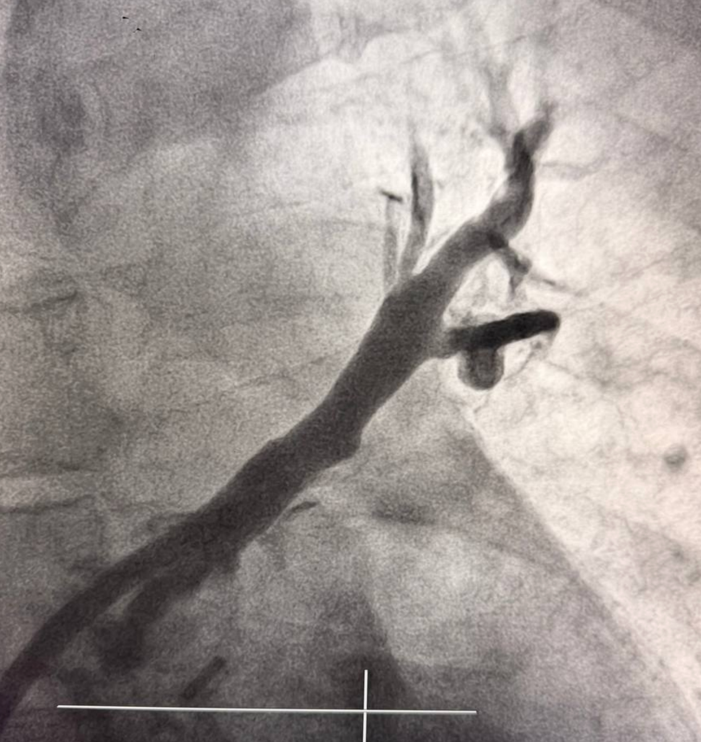

Вмешательство проводилось через бедренный венозный доступ под местной анестезией. Основная сложность операции заключалась в полной окклюзии обеих легочных вен и необходимости точной навигации инструментов в условиях ограниченной визуализации. После реканализации поражённых участков были имплантированы стенты, обеспечившие надёжное восстановление просвета сосудов и полноценный венозный отток из лёгких.

В результате кровоток по левой верхней и левой нижней легочным венам полностью восстановлен. Состояние пациента стабилизировалось, одышка регрессировала. В настоящее время пациент чувствует себя хорошо.